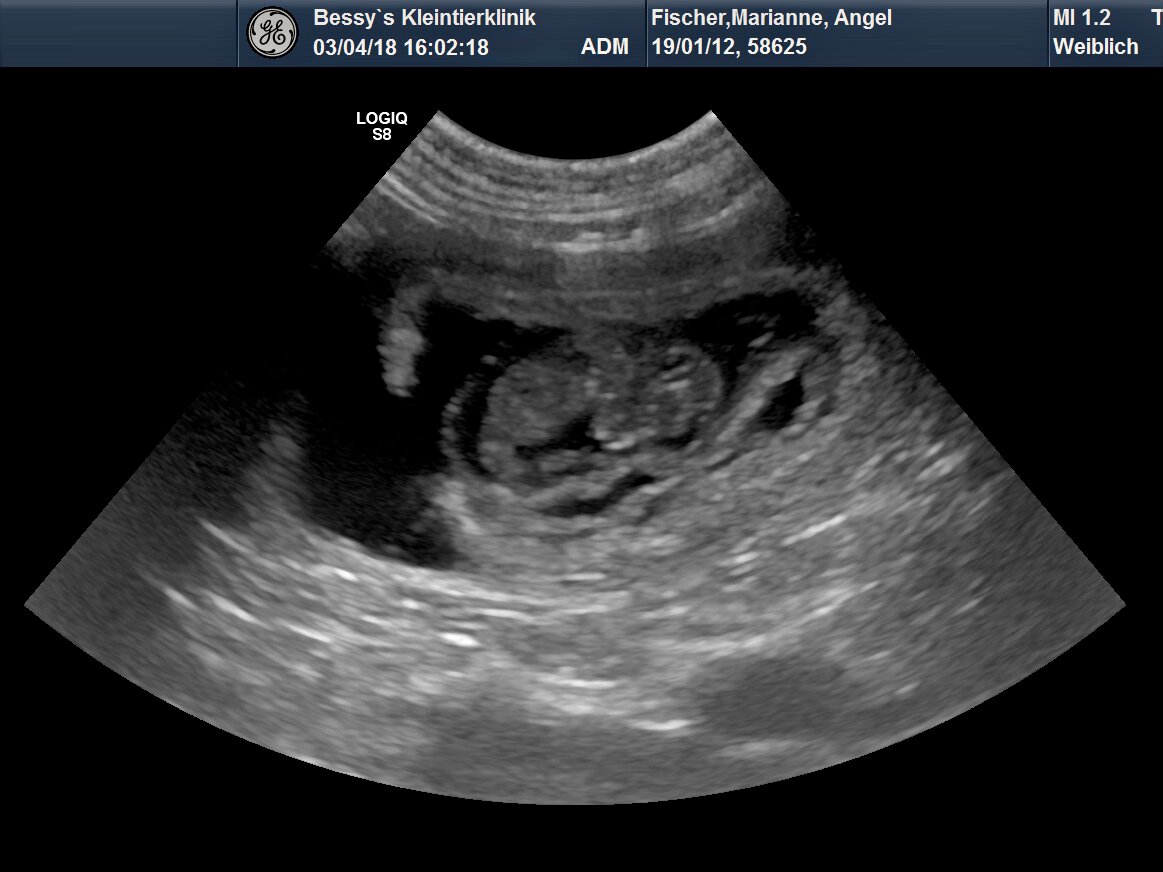

Angel ist definitiv trächtig!

3. April 2018

Bei der heutigen Ultraschall-Untersuchung konnten wir ganz klar 7 kleine Herzen kräftig schlagen sehen! Vielleicht hat sich der eine oder andere Embryo noch irgendwo versteckt aber bald werden wir's wissen - es ist ja jetzt bereits Halbzeit und anfangs Mai sollte der Wurf zur Welt kommen!